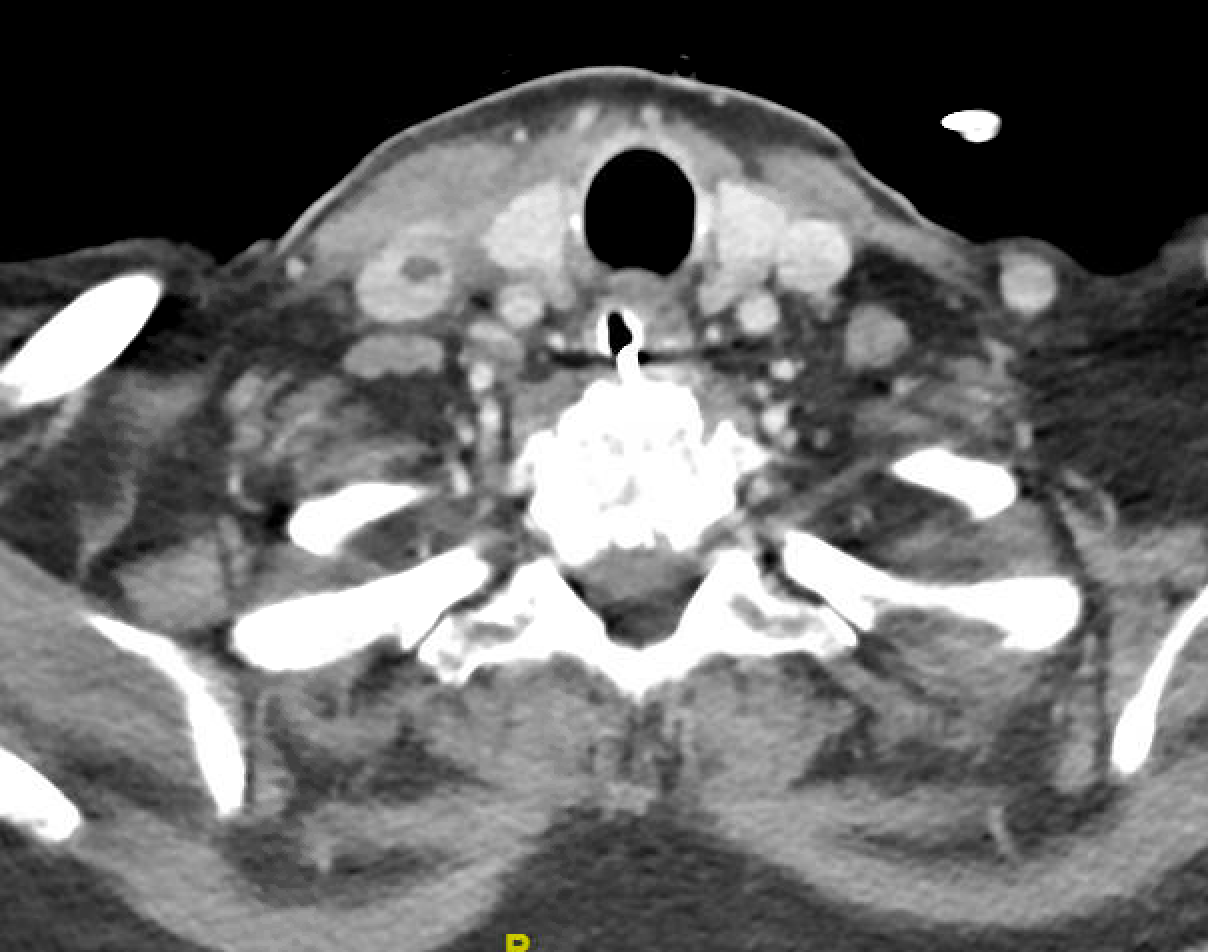

Case Presentation: A 77-year-old female was brought to the emergency with lethargy, confusion, fever for 3 days and neck pain. She had a recent trip to the Caribbean where she was taking Metamizole to manage neck pain. Her physical exam was notable for fever, sinus tachycardia, cervical lymphadenopathy, a muffled voice, and stridor. Initial blood work revealed pancytopenia with an absolute neutrophil count of 0.0. She was started on Cefepime, and a broad infectious workup was started. Viral serologies, blood parasites, and tick-borne illnesses were negative. Laryngoscopy revealed laryngeal edema, and she was intubated for airway protection. Imaging revealed neck edema and lymphadenopathy. Blood cultures were positive for Serratia marcescens. Bone marrow biopsy and flow cytometry were not consistent with malignancy or primary bone marrow failure. Treatment with granulocyte-colony stimulating factor was started, and neutrophil count improved after ten days. It was determined that the most likely etiology of pancytopenia was medication side effect from Metamizole. Cefepime was discontinued after 11 days of treatment and 48 hours without fever. She continued to have persistent cervical lymphadenopathy causing dysphagia, prompting re-evaluation. Repeat imaging demonstrated cervical suppurative lymphadenitis with abscess and a right internal jugular thrombosis, consistent with Lemierre’s syndrome. The abscess was drained and samples again grew S. marcescens. Patient was started on proper antibiotics based on sensitivity. Repeat ultrasound of the thrombus was stable without propagation, therefore anticoagulation was deferred. The patient was successfully discharged after significant clinical improvement.